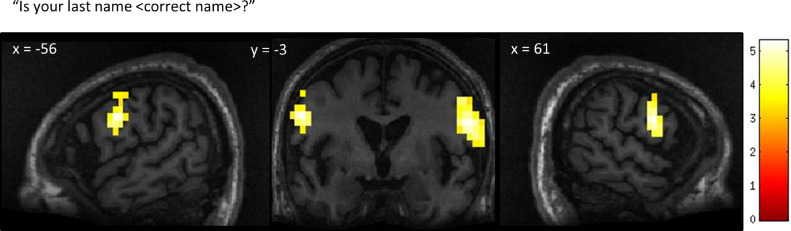

GBS patient 1

The neural activity observed in response to the first question, “Is your last name <incorrect name>?” closely matched the activity observed in the spatial navigation task indicating a ‘no’ response (which, in this case was the correct answer). The second question, “Is your last name <correct name>?” did not elicit activation in the peak region of interest found in either of the mental imagery tasks. However, the patient did display robust significant activation bilaterally in lateral premotor cortex (right lateral PMC T = 5.31, MNI=61,-3,25, k = 59; left lateral premotor cortex T = 4.95, MN=-56,-3,30, k = 33) (Fig. 4). The remaining two questions that pertained to orientation in space (“Are you in the hospital?” and alternatively, “Are you in the supermarket?”) did not yield statistically significant responses, although subthreshold activation was observed in the anatomically appropriate regions (indicating ‘yes’ in response to “Are you in the hospital?” and ‘no’ to “Are you in the supermarket?“). Quantitative analysis of each region of interest within each communication scan in comparison to the localizer scans is shown in Fig. 5.

Fig. 4.

Patient 1’s whole-brain response to a question asking about his correct last name. Significant bilateral activation was observed in the lateral premotor cortex. Results displayed at a peak voxelwise threshold p < .001, uncorrected followed by whole-brain FDR-corrected for significance using cluster extent, p < .05 and displayed on the patient's normalized T1 image.